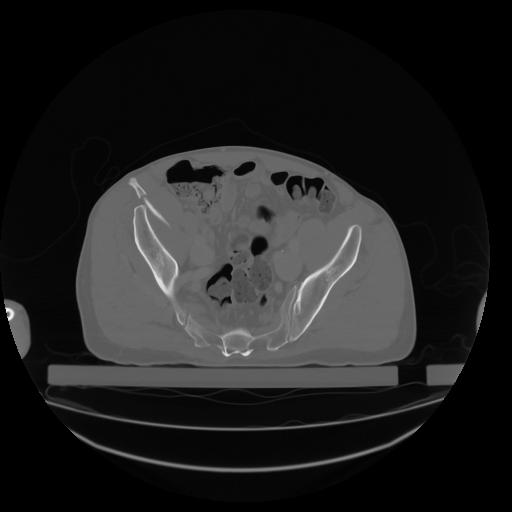

27 CUERPO,CE,Axial,3.0,CUERPO,,